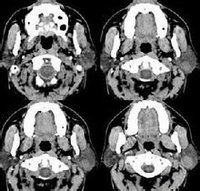

DICOM可明確圖像在數據流傳遞過程中壓縮和加密的格式,並確定CT圖像或B超圖像在資料庫中存儲的方式。

直到近年,界面友好的醫學影像資料庫與二維、三維結構及可視化的結合將醫學影像信息學帶入了一個嶄新的時代。開始於1990年的“可視人”項目提供了大量的人體模擬圖像,這一技術的廣泛套用帶動了各類解剖學教育軟體的開發,更為重要的是引發了關於模型、摸擬及大型數位化圖像搜尋等一系列的信息學問題。同一時間開始的“人類大腦”項目則直接導致了大量關於大腦數據圖譜登記、分Shanghai Med J,2004,VoI27,No9區等課題的開展。新的信息學、生物計量學、計算圖像學的結合,使人們重新認識到影像信息與模擬學的重要性。 現代影像信息學研究的重點包括圖像傳遞標準、傳遞規則、醫學術語、信息壓縮、圖像資料庫索引及圖像病例傳遞安全等。從“虛擬細胞”到“虛擬人”,當前影像信息學從分子水平、細胞水平、組織水平到個體都得到廣泛的套用。然而,醫學信息學面臨著更多亟待解決的現實問題。影像信息的完整化需要更深層的科學、技術和醫療實踐的結合,包括對二維和三維圖像自動分區與註冊的新技術;數據抽象與概括;圖像資料庫中生物多樣性來解釋群體圖像數據和表現型與基因型之間的關係;開發醫學信息數據注釋語言整合高級圖像系統和醫院信息系統等。